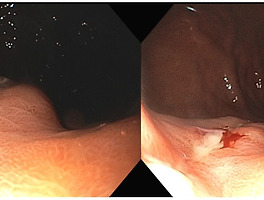

성인에서 lower GI bleeding(LGIB)의 가장 많은 원인은? Hemorrhoid ?

제 의원에 오는 환자들 중에서 LGIB의 가장 많은 원인은 hemorrhoid입니다. 하지만 일반적으로(환자들이 2차, 3차 병원에도 가니깐요) LGIB의 가장 흔한 원인은 diverticulosis입니다(약 15 - 55%). Hemorrhoid는 50세 미만에서 rectal bleeding의 가장 흔한 원인이고, angiodysplasia는 65세 이상에서 가장 흔한 원인입니다(최근 데이터는 이전에 생각했던 것보다 덜 흔할 수 있다고 제안합니다).

Diverticulosis로 인한 출혈은 diverticulosis의 드문 합병증입니다. 그럼에도 불구하고 가장 흔한 원인인 이유는 그만큼 diverticulosis가 유병률이 높기 때문입니다. 40세는 20% 미만이지만 60세는 60%입니다(USA). Diverticular bleeding은 전형적으로 diverticulitis가 없을 때에 발생하며, diverticulitis가 있다고 할지라도 출혈 위험이 더 증가하지는 않습니다.